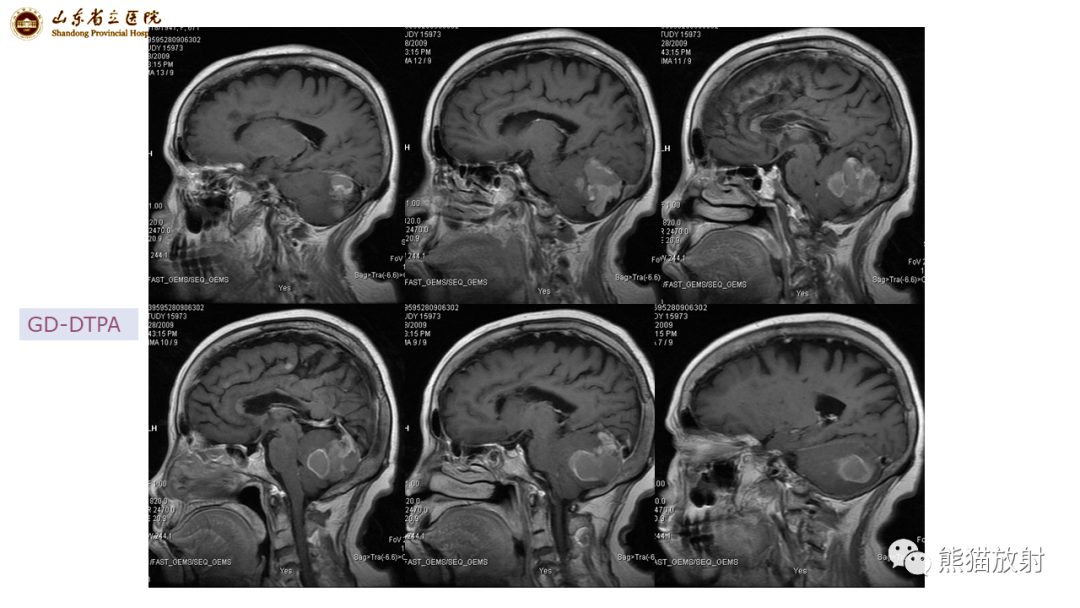

【病例】炎性肉芽肿并脓肿形成 & 成熟性囊性畸胎瘤-3